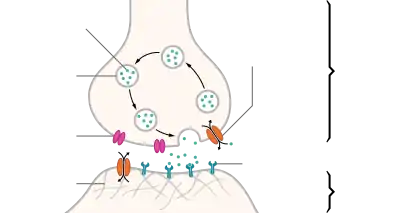

In the absence of caffeine and when a person is awake and alert, little adenosine is present in CNS neurons. With a continued wakeful state, over time adenosine accumulates in the neuronal synapse, in turn binding to and activating adenosine receptors found on certain CNS neurons; when activated, these receptors produce a cellular response that ultimately increases drowsiness. When caffeine is consumed, it antagonizes adenosine receptors; in other words, caffeine prevents adenosine from activating the receptor by blocking the location on the receptor where adenosine binds to it. As a result, caffeine temporarily prevents or relieves drowsiness, and thus maintains or restores alertness.[9]

Caffeine is an antagonist of adenosine A2A receptors, and knockout mouse studies have specifically implicated antagonism of the A2A receptor as responsible for the wakefulness-promoting effects of caffeine.[163] Antagonism of A2A receptors in the ventrolateral preoptic area (VLPO) reduces inhibitory GABA neurotransmission to the tuberomammillary nucleus, a histaminergic projection nucleus that activation-dependently promotes arousal.[164] This disinhibition of the tuberomammillary nucleus is the downstream mechanism by which caffeine produces wakefulness-promoting effects.[164] Caffeine is an antagonist of all four adenosine receptor subtypes (A1, A2A, A2B, and A3), although with varying potencies.[9][163] The affinity (KD) values of caffeine for the human adenosine receptors are 12 μM at A1, 2.4 μM at A2A, 13 μM at A2B, and 80 μM at A3.[163]

Antagonism of adenosine receptors by caffeine also stimulates the medullary vagal, vasomotor, and respiratory centers, which increases respiratory rate, reduces heart rate, and constricts blood vessels.[9] Adenosine receptor antagonism also promotes neurotransmitter release (e.g., monoamines and acetylcholine), which endows caffeine with its stimulant effects;[9][165] adenosine acts as an inhibitory neurotransmitter that suppresses activity in the central nervous system. Heart palpitations are caused by blockade of the A1 receptor.[9]

Because caffeine is both water- and lipid-soluble, it readily crosses the blood–brain barrier that separates the bloodstream from the interior of the brain. Once in the brain, the principal mode of action is as a nonselective antagonist of adenosine receptors (in other words, an agent that reduces the effects of adenosine). The caffeine molecule is structurally similar to adenosine, and is capable of binding to adenosine receptors on the surface of cells without activating them, thereby acting as a competitive antagonist.[166]